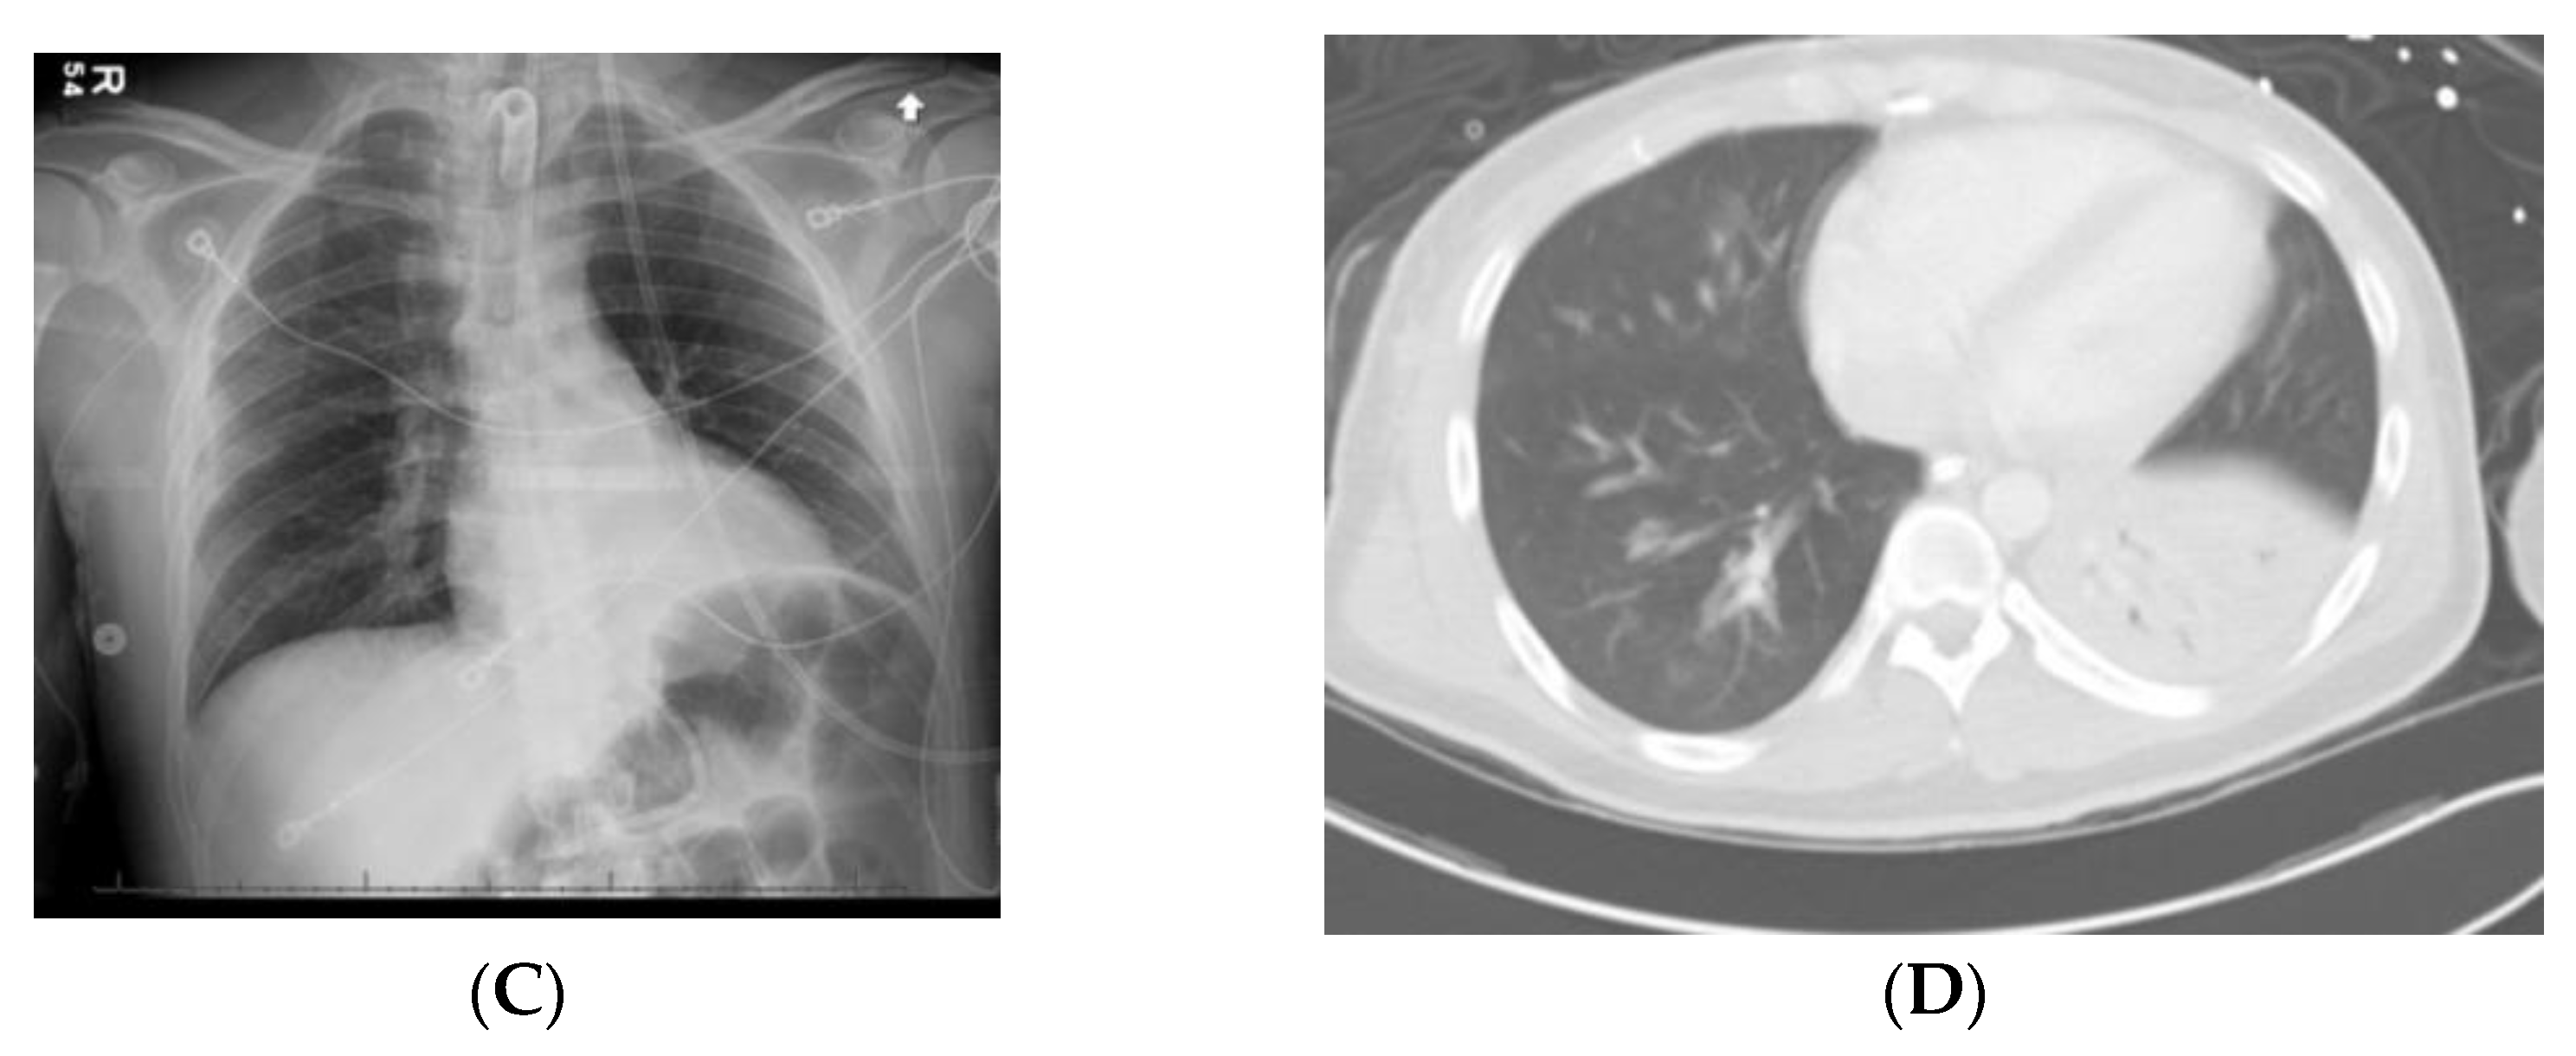

6.2. Case 2